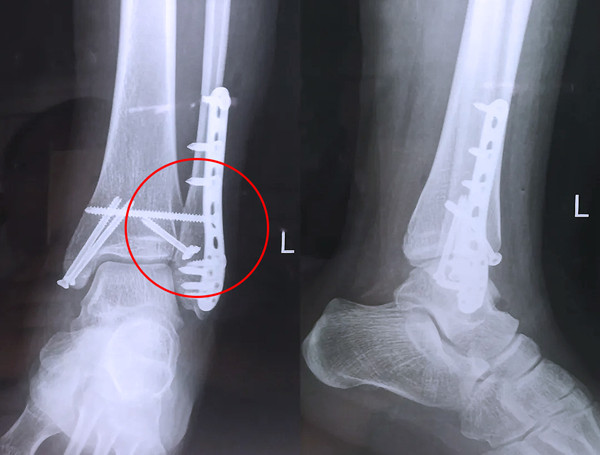

踝關節骨折在X影像上的表現有很多種。如內踝骨折和外踝骨折,我們可以在影像上看到骨折處的骨折線是不連續的。還有后踝的骨折,內踝、外踝、后踝聯合在一起發生的骨折,我們稱之為“三踝骨折”,這些都是在X影像上能夠顯示出來的。

內踝骨折

外踝骨折

后踝骨折

三踝骨折